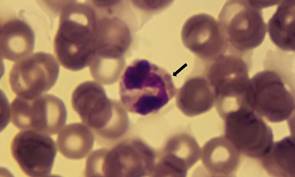

En la revisión de los frotis teñidos se encontraron las mórulas características de la infección por Ehrlichia spp.Figuras 1 y 2.

Figura 1 Frotis sanguíneo 1000x, en él se ve un glóbulo blanco con mórulas de la bacteria dentro del citoplasma (flecha).